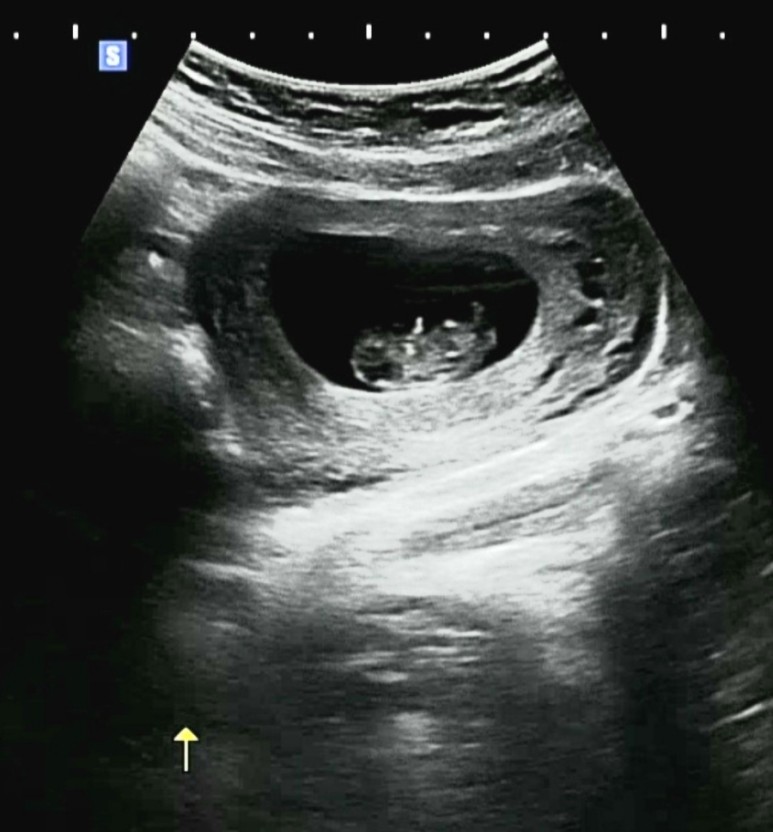

그리고 기다리던 우리 따복 초음파! 못 본 사이에 정말 쑥쑥 컸어 🙂 젤리곰이 너무 귀여워서 세상사람들한테 자랑하고 싶었어 ㅋㅋㅋㅋㅋㅋㅋㅋ